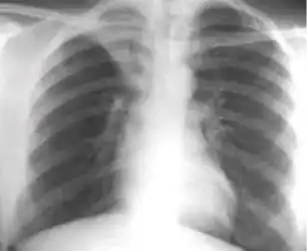

Radiology (X-rays) is used in the diagnosis of tuberculosis. Abnormalities on chest radiographs may be suggestive of, but are never diagnostic of TB, but can be used to rule out pulmonary TB.

A posterior-anterior (PA) chest X-ray is the standard view used; other views (lateral or lordotic) or CT scans may be necessary.

In active pulmonary TB, infiltrates or consolidations and/or cavities are often seen in the upper lungs with or without mediastinal or hilar lymphadenopathy.[1] However, lesions may appear anywhere in the lungs. In HIV and other immunosuppressed persons, any abnormality may indicate TB or the chest X-ray may even appear entirely normal.[1]

Abnormalities on chest radiographs may be suggestive of, but are never diagnostic of, TB.[1] However, if a person has a positive response to the tuberculin skin test and no symptoms of the disease, chest radiographs can be used to rule out the possibility of pulmonary TB.